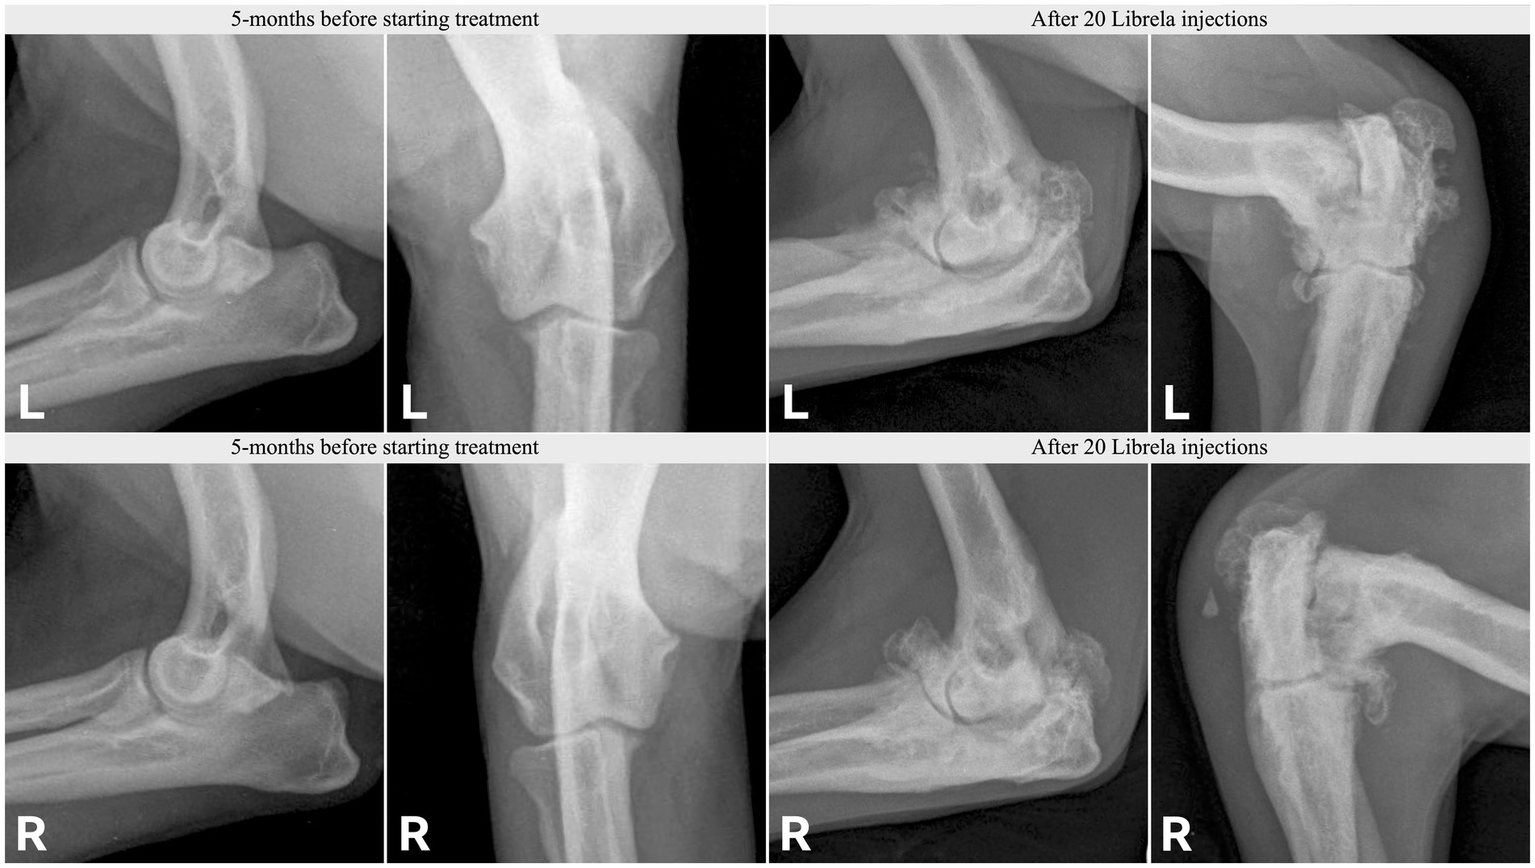

Figure 11

Radiographs from Case 17, a 5-year-old Springer Spaniel, before and after 20 Librela injections.

Figure 12

Case 18, a 5.5-year-old Australian Shepherd, had stable stifle joints before starting Librela. AER: The attending specialist filed a report for suspected RPOA to the MAH, who submitted an AER for ligament ruptures, fractures, and joint subluxation/luxations. Their report designated this reaction as not serious (Supplementary Figure S9).